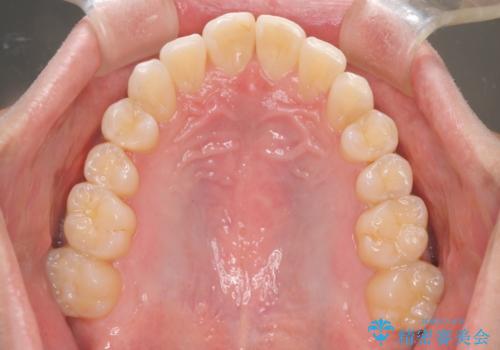

初診時の歯並びの状態としては、上下ともに前歯部の中等度のがたつきがあり、上の前歯が重なっている状態でした。

また元々下の前歯は1本少なく、歯の本数が少ないことを前提とした矯正治療を行いました。

抜歯は必要なく、マウスピース矯正にて治療を行っています。